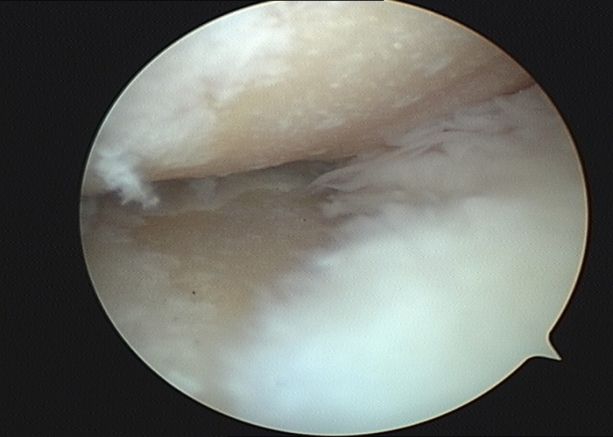

第三階梯:修復(fù)性治療。當(dāng)保守治療無法滿意控制病情時,可考慮微創(chuàng)或矯形手術(shù)。①關(guān)節(jié)鏡清理術(shù):通過微創(chuàng)切口,清除關(guān)節(jié)內(nèi)的炎性滑膜、破碎的軟骨和游離體。②截骨術(shù):通過矯正下肢力線,將身體重量從磨損嚴(yán)重的一側(cè)轉(zhuǎn)移到相對健康的一側(cè)。